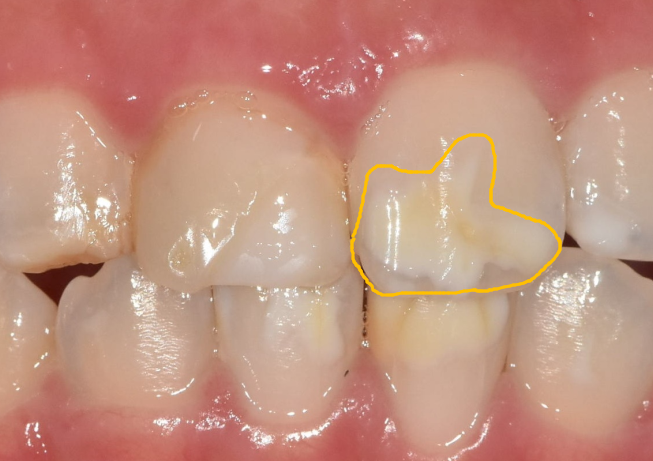

특히 왼쪽 송곳니는 탈회가 진행돼서 초기 충치로 변하고 있는 상태였어요.

충치가 진행된 모습

양측 송곳니를 보니,

반대편 치아와 물리는 부분이 너무 긴밀합니다.

쉽게 말하면, 위 치아가 아래 치아를 덮지 않고 씹는 면 끝과 끝이 물리더라고요.

이런 경우 라미네이트를 하면

깨질 가능성이 높습니다.